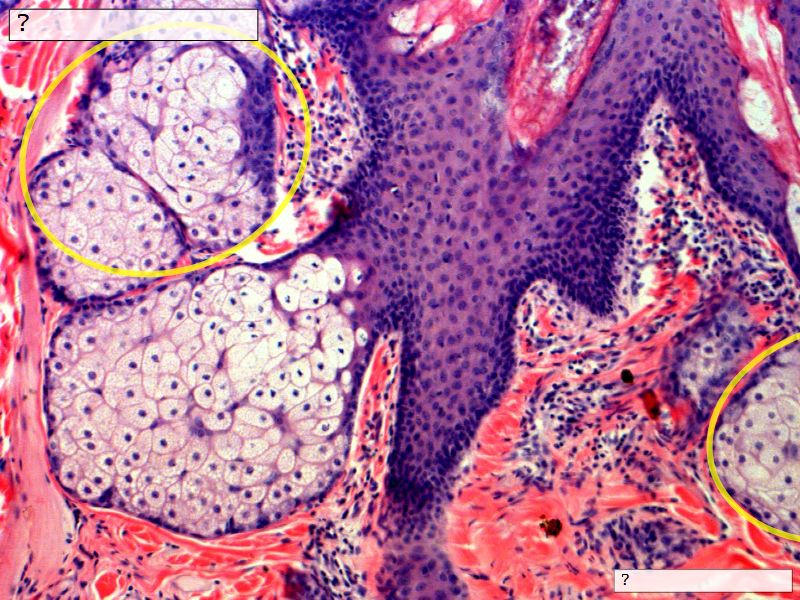

Fill in all the missing labels, and assess as you move through the slides. Answers on the down slide. It is important to do this using pen and paper, and not just glance through the images.